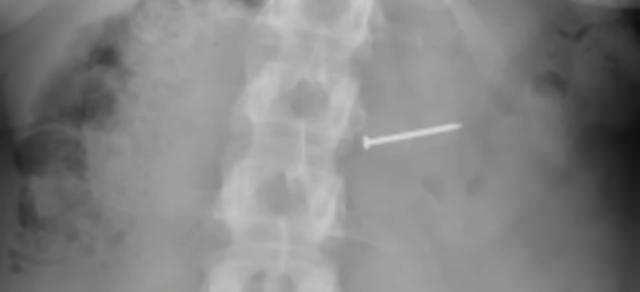

Dondurmayı yediği anda boğazında sert bir parça olduğunu hisseden Buckley, başlangıçta ceviz parçası olduğunu düşündü ancak can acıtan durumun devam etmesiyle soluğu hastanede aldı. Yapılan röntgen incelemesi sonucunda kadının yuttuğu cisimin ceviz değil, metal bir çivi olduğu ortaya çıktı.

Yaşanan skandalın ardından genç kadının dondurmasında birden fazla çivi ve keskin metal kalıntısı olduğu tespit edildi. Baş, boyun ve sinir sistemi başta olmak üzere vücudunun çeşitli bölgelerinde kalıcı hasar meydana gelen genç kadının sağlık raporlarında, fiziksel izlerin yanı sıra uzun süreli nörolojik sorunların da devam ettiği bilgisi yer aldı. Buckley, ayrıca yaşadığı olayın ardından çocuk sahibi olma ihtimalinin ortadan kalktığını da açıkladı.